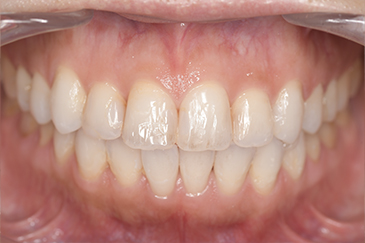

CASE 14

下顎before

下顎after

| 年齢・性別 | 27歳・男性 |

|---|---|

| 主訴 | 歯石とりたい |

| 治療内容 | スケーリング |

| 治療期間 | 30分 |

| 治療費 | 約1,500円(保険診療) |

| リスク・副作用 | 知覚過敏、歯肉退縮、出血 |

| 治療方針 | 歯列不正でプラークがつきやすいため、TBIを行い定期的に歯石を除去していきます。 プラークコントロールが出来るようになったら定期検診でクリーニングを行っていきます。 |